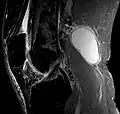

Die Diagnose wird neben der klinisch-manuellen Untersuchung durch Ultraschall (Sonographie) und evtl. eine Kernspintomographie erhärtet; dabei werden auch Differentialdiagnosen wie Aneurysmen der Popliteal-Arterie oder -vene[3] ausgeschlossen.